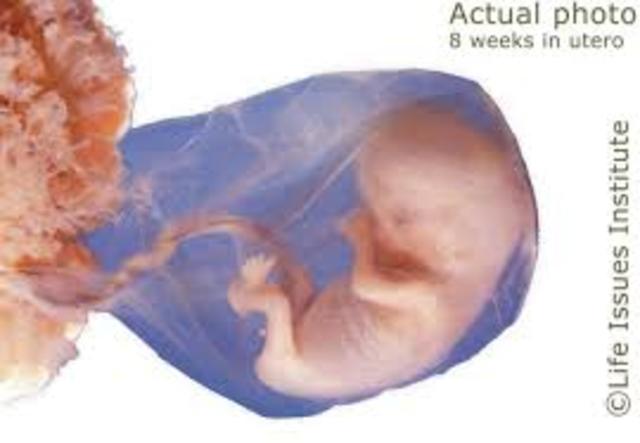

• 2nd Month (Weeks 8-10)

2nd Month (Weeks 8-10)

Week 8-

End of embryonic stage

Size of a kidney bean

Facial features are more defined

Nerve cells are forming neural pathways

Part responsible for scent is taking shape

Arms and legs are lengthened

Ankles, thighs, knees and toes are not as defined

embryonic tail is almost gone